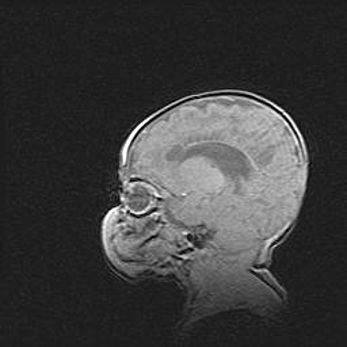

Аномалия Денди-Уокера. Признаки гипоплазии мозолистого тела.

Возраст: 5 месяцев 3 дня

Вес: 5550 г

Пол: мужской

Окружность головы: 39 см

Срок гестации: 40 недель

Аномалия Денди-Уокера – это порок развития головного мозга, для которого характерна триада симптомов: гипотрофия или аплазия червя мозжечка и/или полушарий мозжечка, расширение четвёртого желудочка с формированием ликворной кисты задней черепной ямки, гипертензионная гидроцефалия различной степени.

Гипоплазия мозолистого тела относится к дефектам внутриутробного этапа развития мозговой ткани, возникающим в процессе закладки структур головного мозга, что происходит на начальных этапах развития эмбриона.